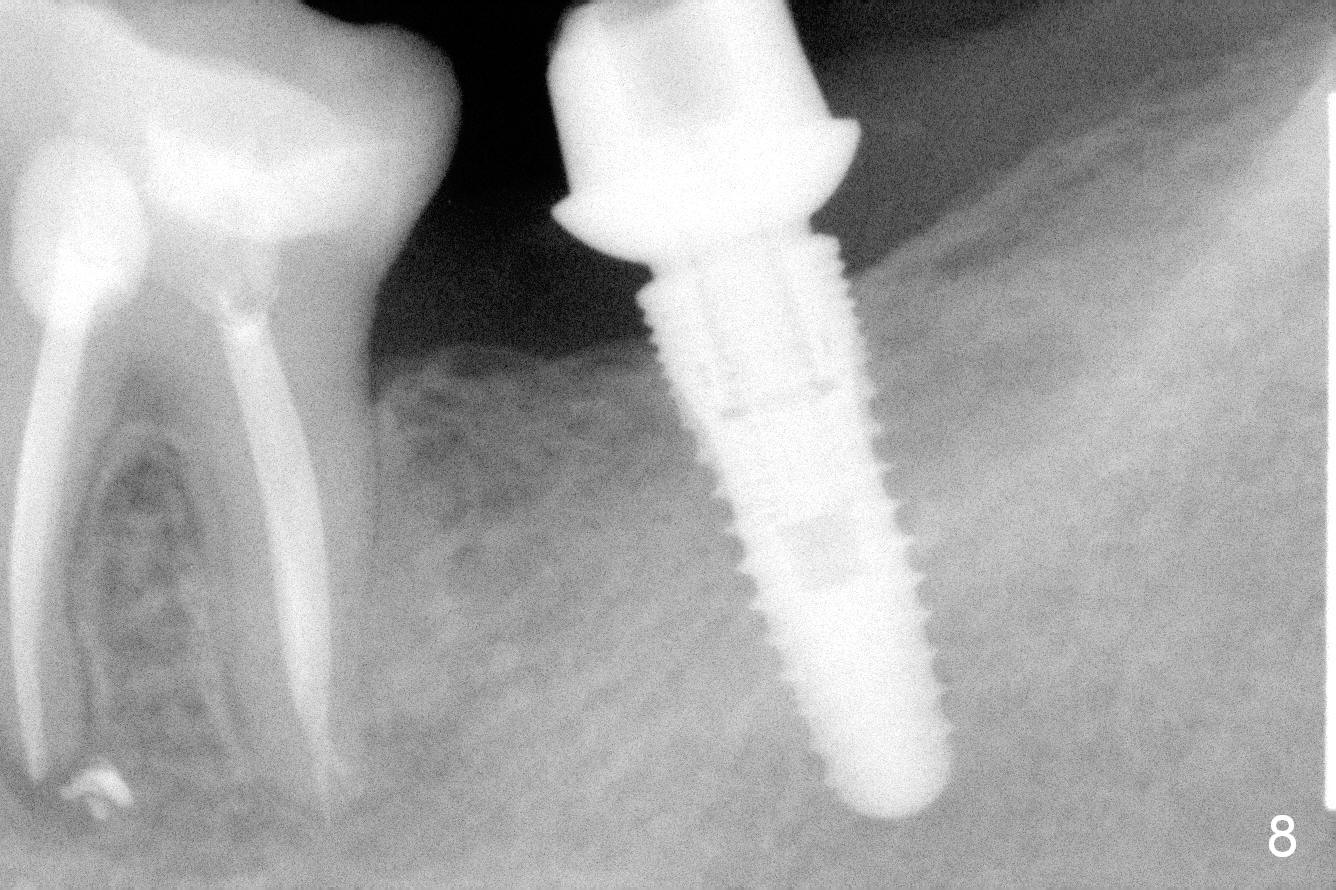

Planning gives the surgery and assistants confidence. Implant placement seems to be more smoothly. A preop PA (Fig.1) shows that the periapical radiolucency of the neighboring tooth #19 disappears. Removal of the residual roots of the teeth #17 and 18 (Fig.1 *) gives rise to a nice surgical field (Fig.2, the sockets packed with Clindamycin soaked gauze). Immediate implant osteotomy is formed as mesial as possible of the wound. Attention is being paid to buccolingual trajectory when the first pilot drill is used (not shown). An intraop PA is taken with a 3.8 mm tap in place to confirm the depth of the osteotomy relative to the inferior alveolar canal (Fig.3). A 4.5x12 mm implant is placed as planned (Fig.4). The elongated wound (mesiodistally) allows the wound to approximate around the implant/healing abutment with sutures (Fig.5). The gingiva heals 8 days postop (Fig.6). The 1st 4 coronal threads remains outside the bone 3.5 months postop (Fig.7 >). It appears that less thread exposure 1 year 7 months postop (Fig.8), suggesting bone growth. To prevent periimplantitis and facilitate restoration, place 2nd molar implant as deep as possible with slightly shorter implant.